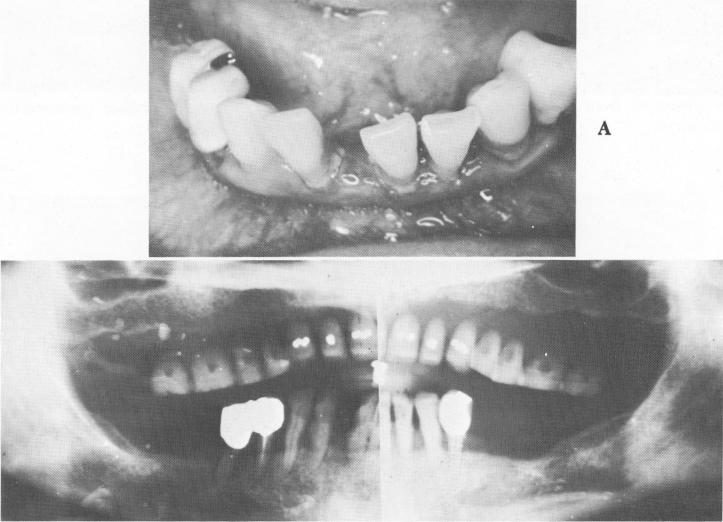

Fig. 13-57. A, The existing teeth were extremely loose. B, A Panorex shows very little sup-porting bone.